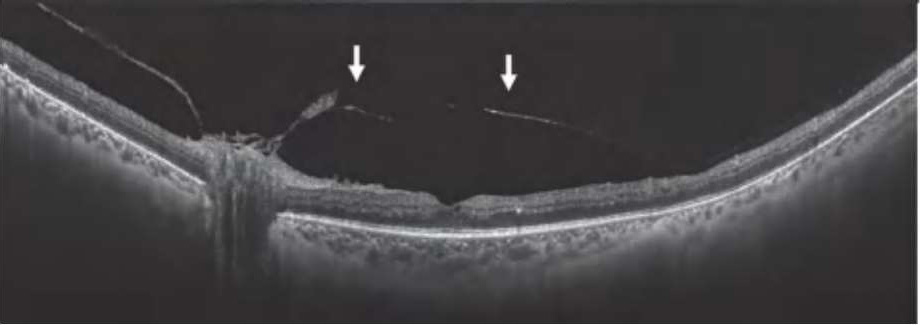

图2-2-1 抗VEGF及PRP治疗后玻璃体后脱离范围显著扩大的PDR案例

A.PDR合并玻璃体视网膜牵拉引发的相关DME,既往已行PRP,行4次抗VEGF药物治疗后,黄斑区玻璃体后界膜与视网膜分离(白色箭头所示),玻璃体视网膜牵拉解除,黄斑水肿较前明显好转。B.PDR合并玻璃体视网膜牵拉性相关DME,在行3次视网膜激光光凝治疗后,黄斑区玻璃体后界膜与视网膜分离(白色箭头所示),玻璃体视网膜牵拉缓解,黄斑水肿较前好转。